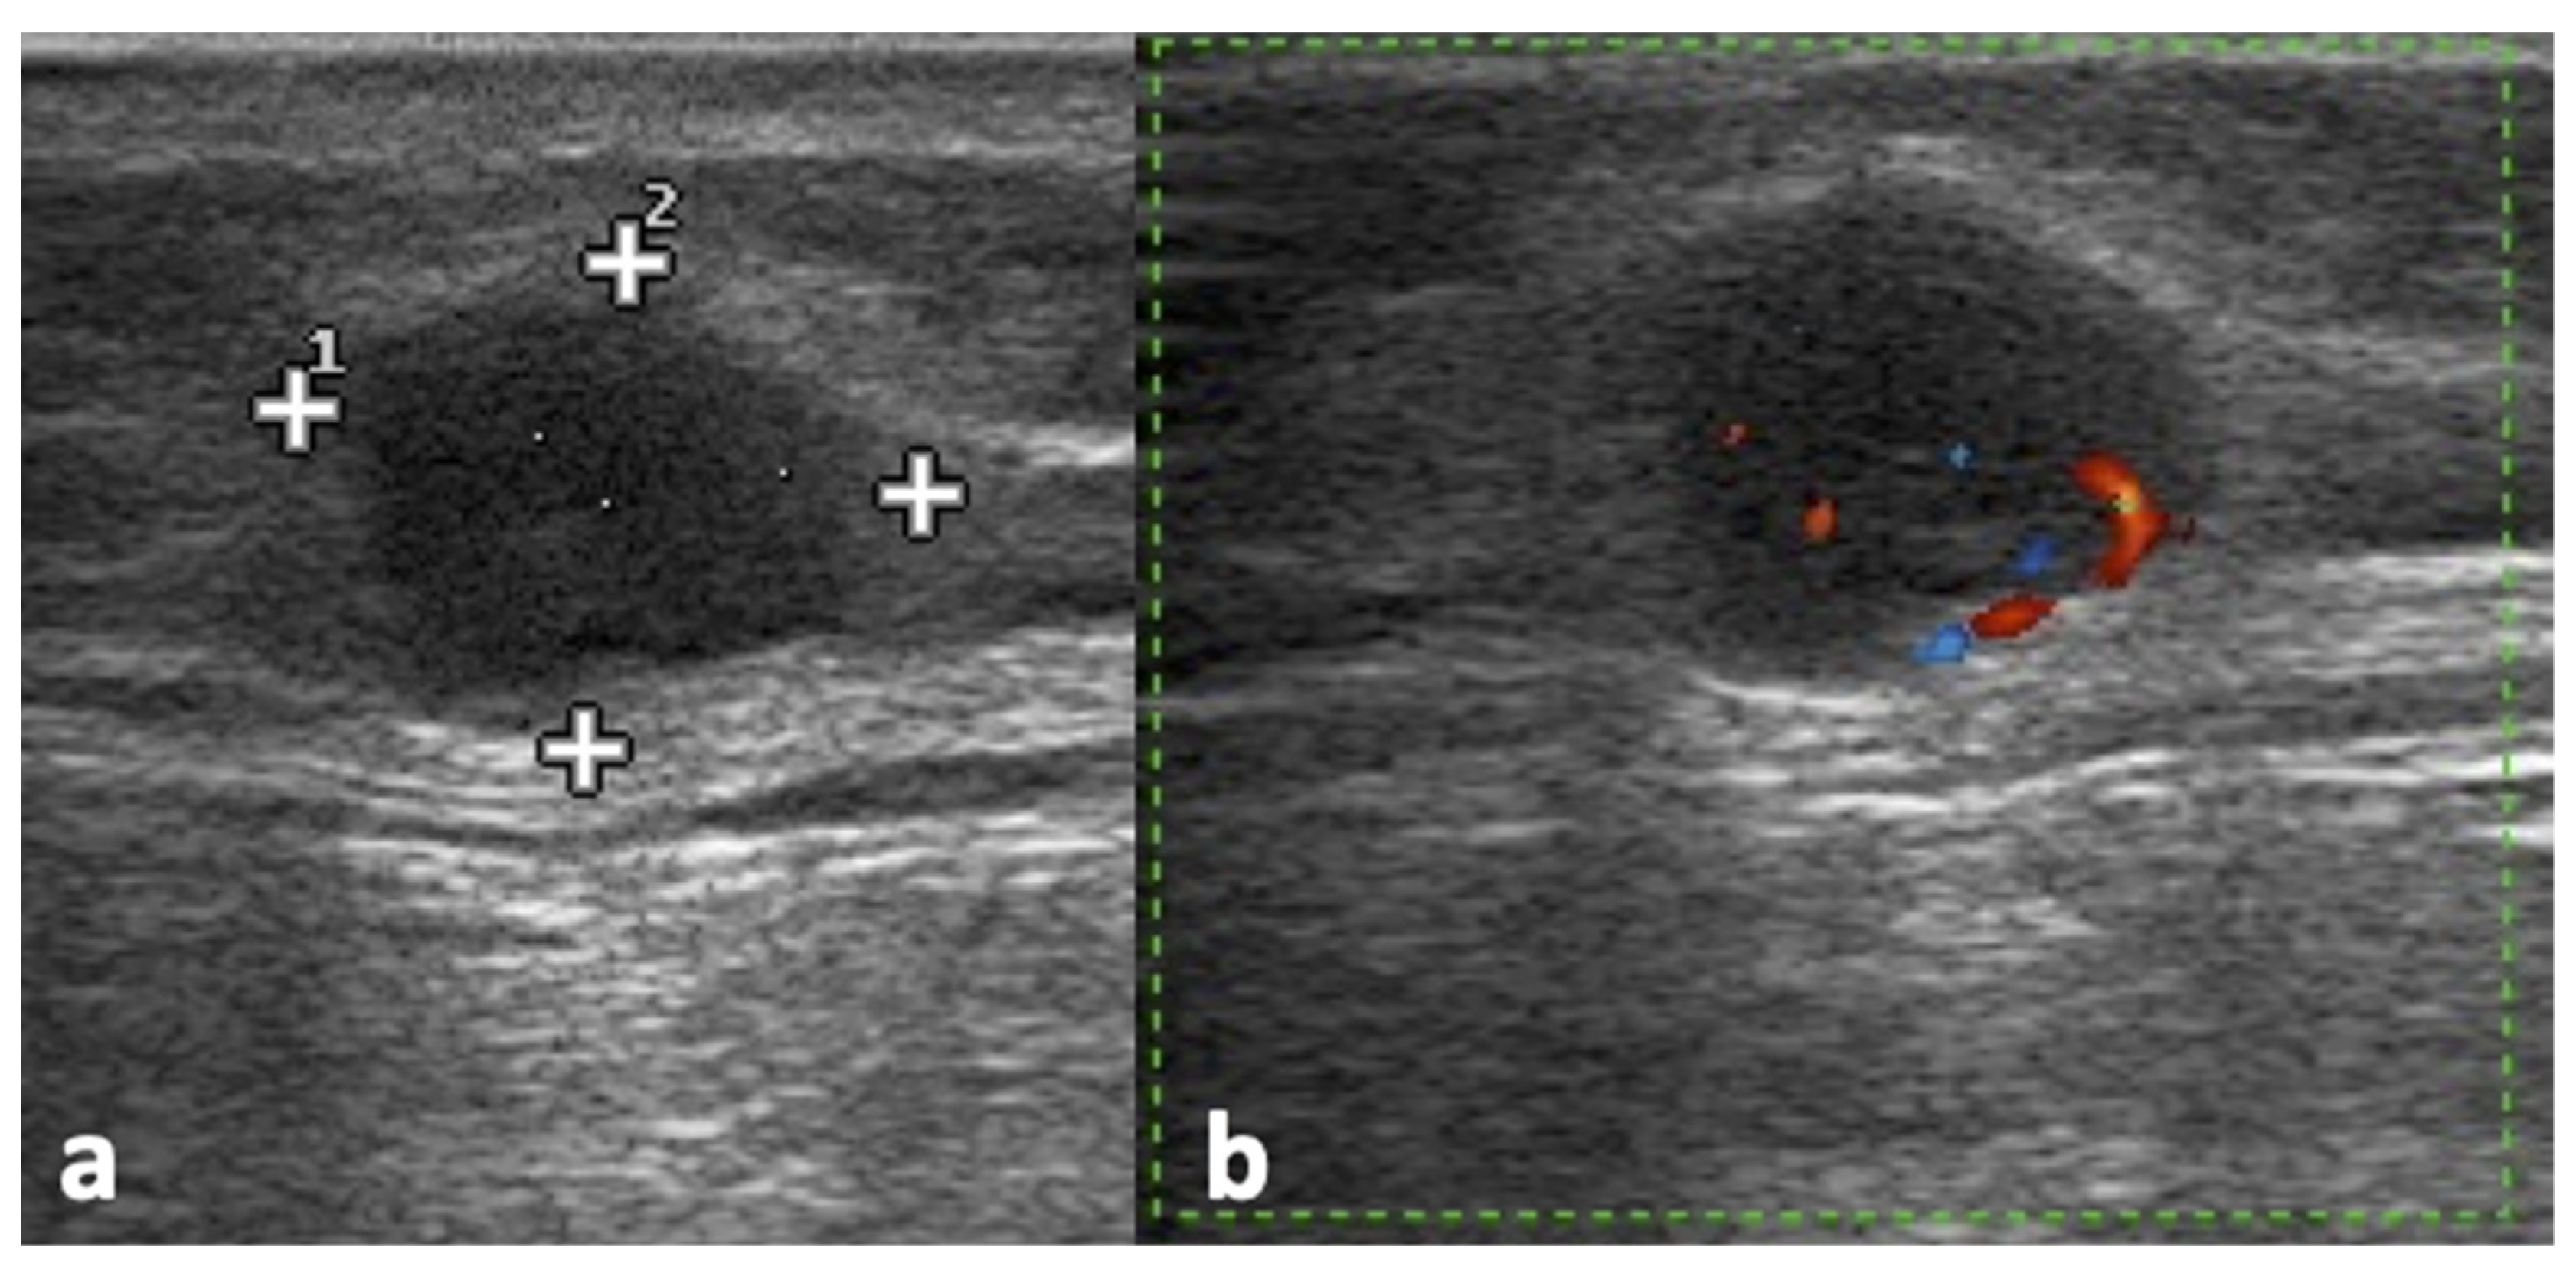

2.4. Ultrasound Assessment

2.5. Assessment with Other Imaging Techniques (CT, MRI, PET)